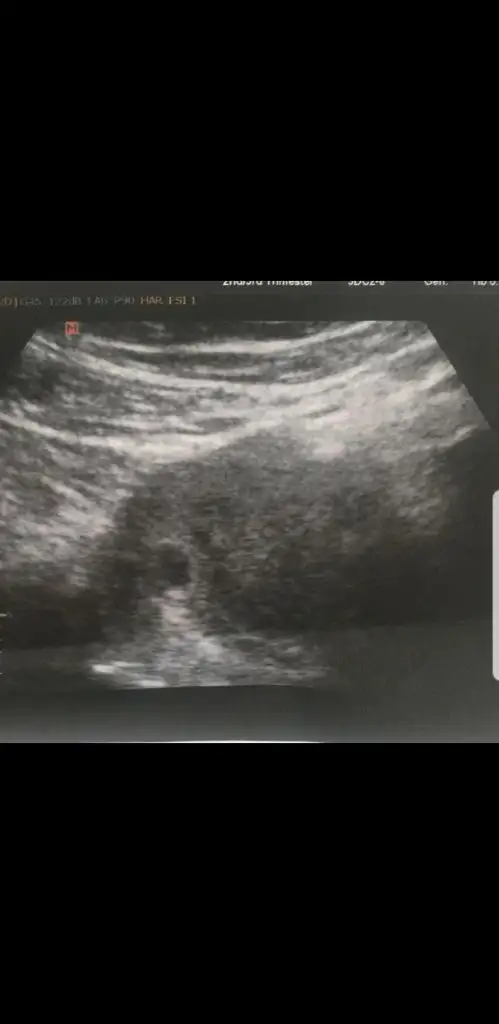

Merhaba hanımlar. Ne güzel haberler gelmiş pıt pıtlar duyulmuş. Bizim gelinin durumu hala belli değil. Salı günü biraz kanaması olmuş. Hemen doktora gitmiş. Doktor alttan bakmış. Gelişim yok bebekte yok demiş. P tesi gel kürtaja demiş. Bizim gelin de başka bir hastaneye gitmiş. Ordaki doktor kese düzgün kordon var demiş. Haftaya tekrar bakalım demiş. Aklı iyice karıştı. Kesenin ölçüsü yine yok.

Nedense ölçmüyorlar keseyi. Sat 20 eylül. Buna göre 7.hafta olması lazım. 5 haftalık demiş. Geçen haftada gittiğinde 5 haftalık demişlerdi.. ultrason görüntülerini yüklüyorum. Yorumlarınızı bekliyorum

Eklentiler

• Screenshot_20191107-224958_WhatsApp.webp

Screenshot_20191107-224958_WhatsApp.webp

10 KB · Görüntüleme: 51

• Screenshot_20191107-224930_WhatsApp.webp

Screenshot_20191107-224930_WhatsApp.webp

12,3 KB · Görüntüleme: 55